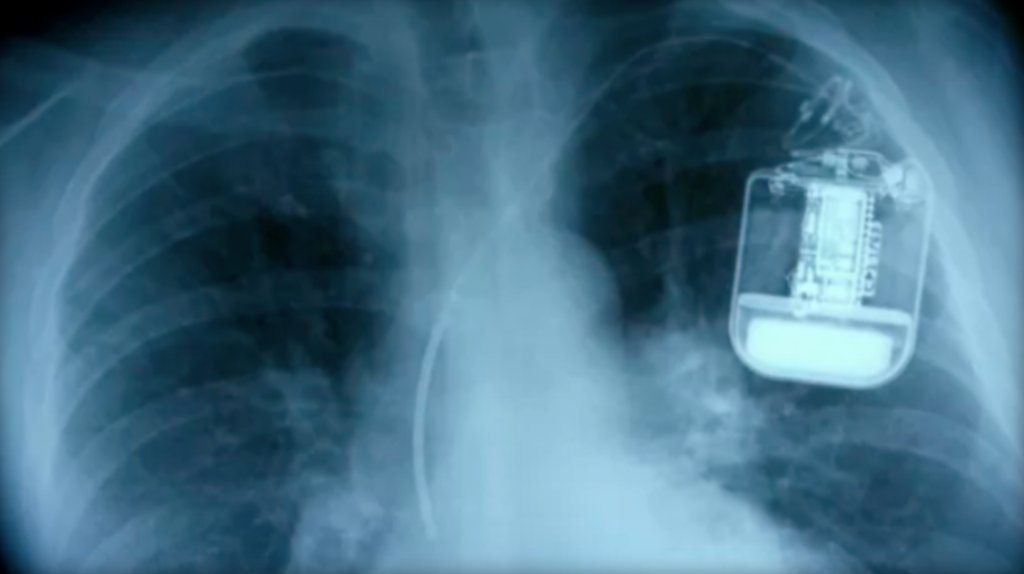

And CBS has a slightly dated stock photo library